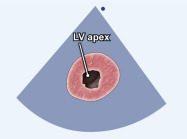

| 2.13. Mặt cắt trục ngắn cạnh ức (ngang mức mỏm tim) |

||||||||

|

|

Cửa sổ siêu âm cạnh ức

Mặt cắt trục ngắn cạnh ức Từ vị trí các cơ nhú gập đầu dò xuống dưới |

Mỏm thất trái (LV apex) | |||||